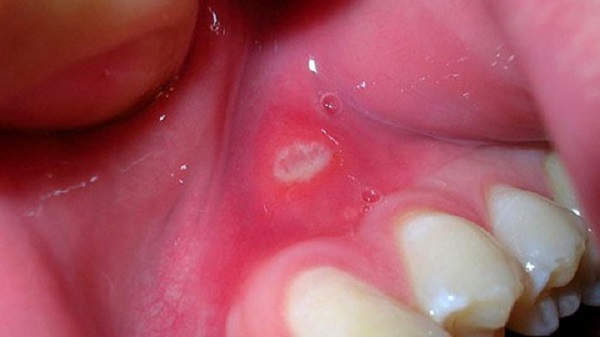

Афтозный стоматит – один из видов воспаления слизистой оболочки рта. Свое название болезнь получила из-за симптомов в виде появления язв (афт) во рту. Данные проявления очень болезненны, могут возникать как поодиночке, так и массово. Внешне афты имеют овальную, чаще круглую форму, с четкими розовыми или красными границами. Появляться такие ранки могут на внутренней стороне губ, языке, небе, щеках. Раны имеют разный размер от 3,5 мм и больше.

Стоматит такого типа может возникнуть у людей всех возрастов, реже им болеют грудные и маленькие дети до 3 лет. Проявление болезни начинается со жжения и болезненности слизистых покровов рта, чувства недомогания. Длится заболевание достаточно долго, от появления афт и до полного их заживления иногда требуется 7-14 дней. Рассмотрим более подробно признаки воспаления.